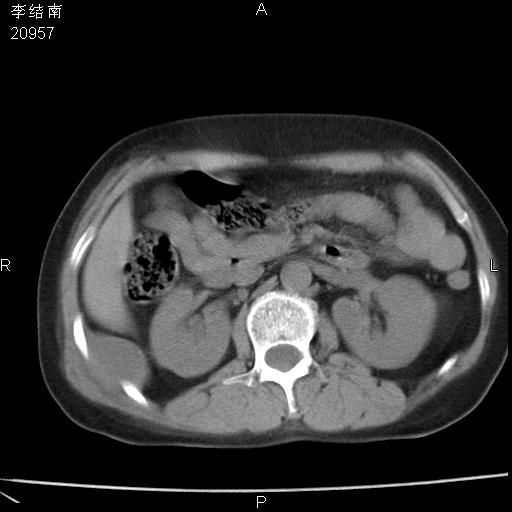

患者女,45岁,以右侧腰部包块来就诊,局部有压痛,皮肤颜色正常。因为是熟人扫的范围较大,患者有胆结石,胆源性胰腺炎病史。请大家看看,有手术病理。

可能大家觉得片子的质量不好,当时是做下腹部扫描,所以没有常规喝水,右腹壁的病灶当时是,密度不均有钙化影,局部骨质没见破坏,肝脏应该是受压的表现,所以当时考虑为腹壁的良性占位,各位老师考虑的神经源性肿瘤,我当时还真没想到,胰腺是胰腺炎治疗后改变.膈脚旁的混杂密度包快不好考虑什么,到上级医院做增强(腹部)+肺部平扫后,发现腹壁的病灶呈不均匀性强化局部可见囊性灶,当时考虑为腹壁结核,最具戏剧性的是膈脚旁的混杂密度灶确是胃的一部分,而腹壁的病灶确是脂肪瘤(简直不可思议)但是我亲眼所见在我们县医院开的.

很不好意思 ,患者后来手术切口裂开,临床医生作了病理证实是腹壁结核。

[病理诊断] CT13183腹壁结核!